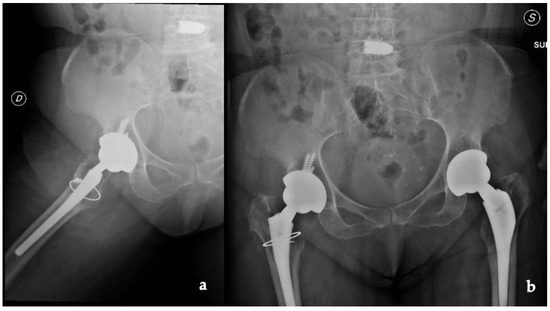

2. Case Report